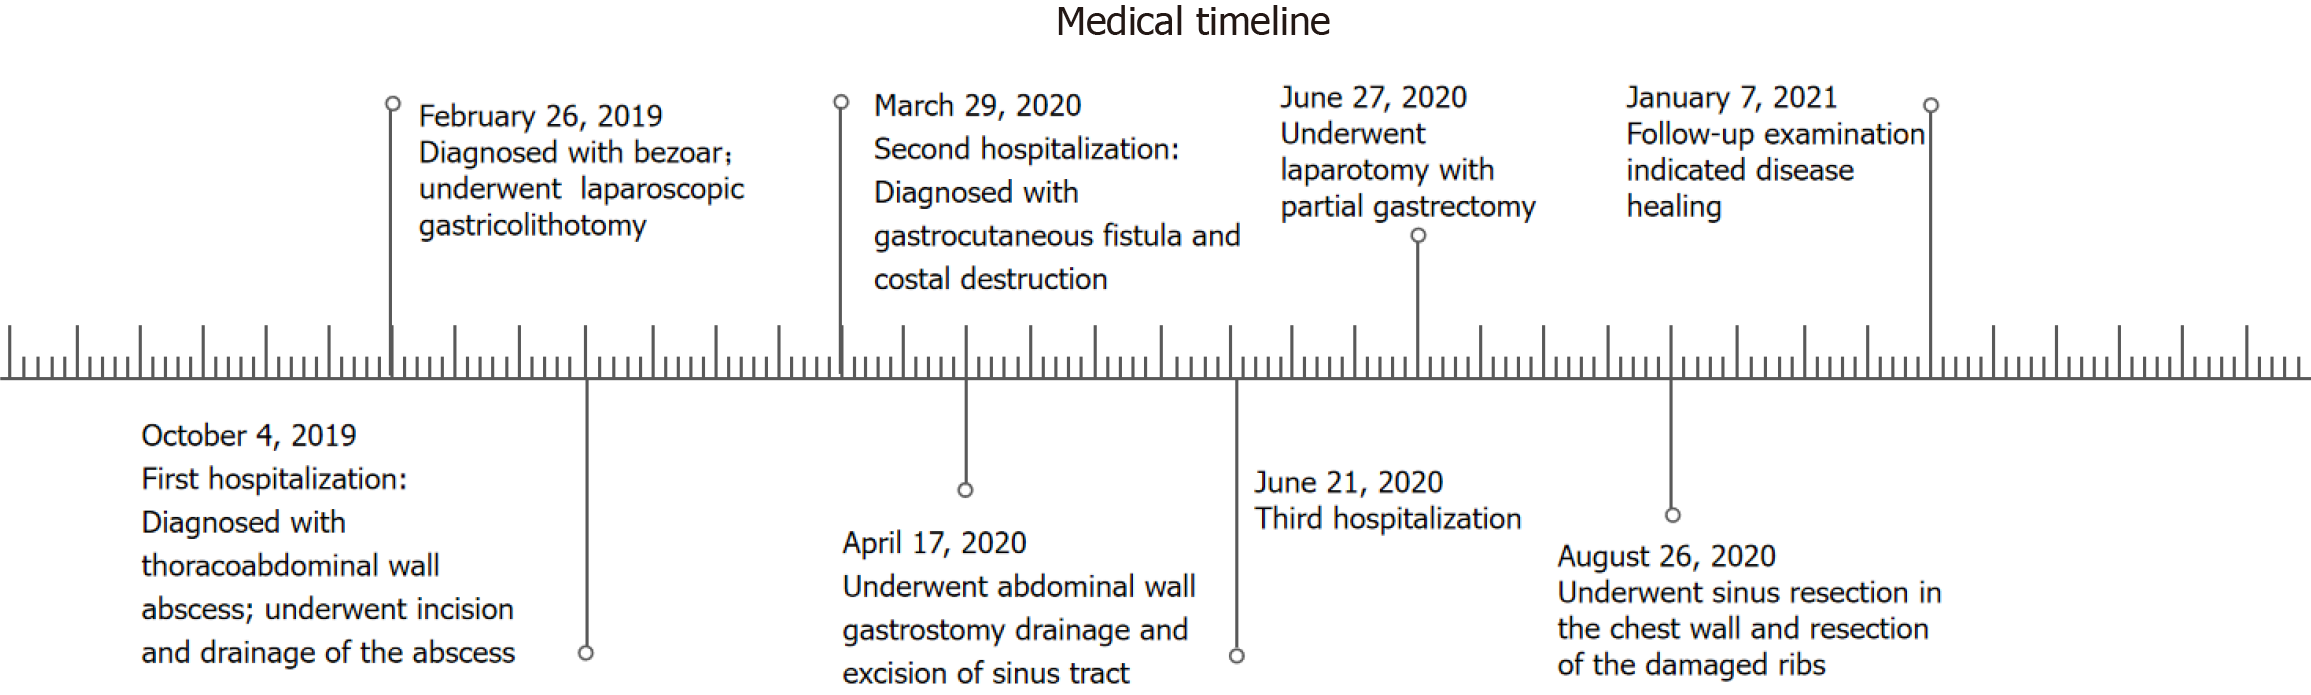

Here we report a 67-year-old man who suffered for 18 months and underwent surgery several times due to a rare and undetected complication of laparoscopic gastricolithotomy. He presented to multiple hospitals because of sustained left upper quadrant abdominal pain one month after laparoscopic gastricolithotomy due to a large gastric bezoar caused by unrestrained eating of black dates and was diagnosed with possible intercostal neuritis. Many painkillers were used to relieve his symptoms but the condition progressed. Seven months after surgery, he was hospitalized as skin ulceration occurred in the left upper abdominal wall and was subsequently diagnosed with a massive thoracoabdominal wall abscess. One year after surgery, irreversible costal destruction was demonstrated. Both lesions were finally proved to be secondary damage due to a rare chronic gastro-abdominal wall fistula related to laparoscopic gastricolithotomy and the diameter of the gastric fistula reached 2 centimeters (cm). The patient was ultimately cured but underwent multi-regional incisions and drainage of the abscess, drainage of the gastric fistula, partial gastrectomy and removal of damaged ribs, and was fo

Although the patient was discharged with mild pain on September 14, 2020, we were confident that he would have a complete recovery and it was proved by reexamination 3 months later (Figure 7). The patient was then followed up for more than 4 years without recurrence. Time-line about diagnosis and treatment of the patient was shown on Figure 8.